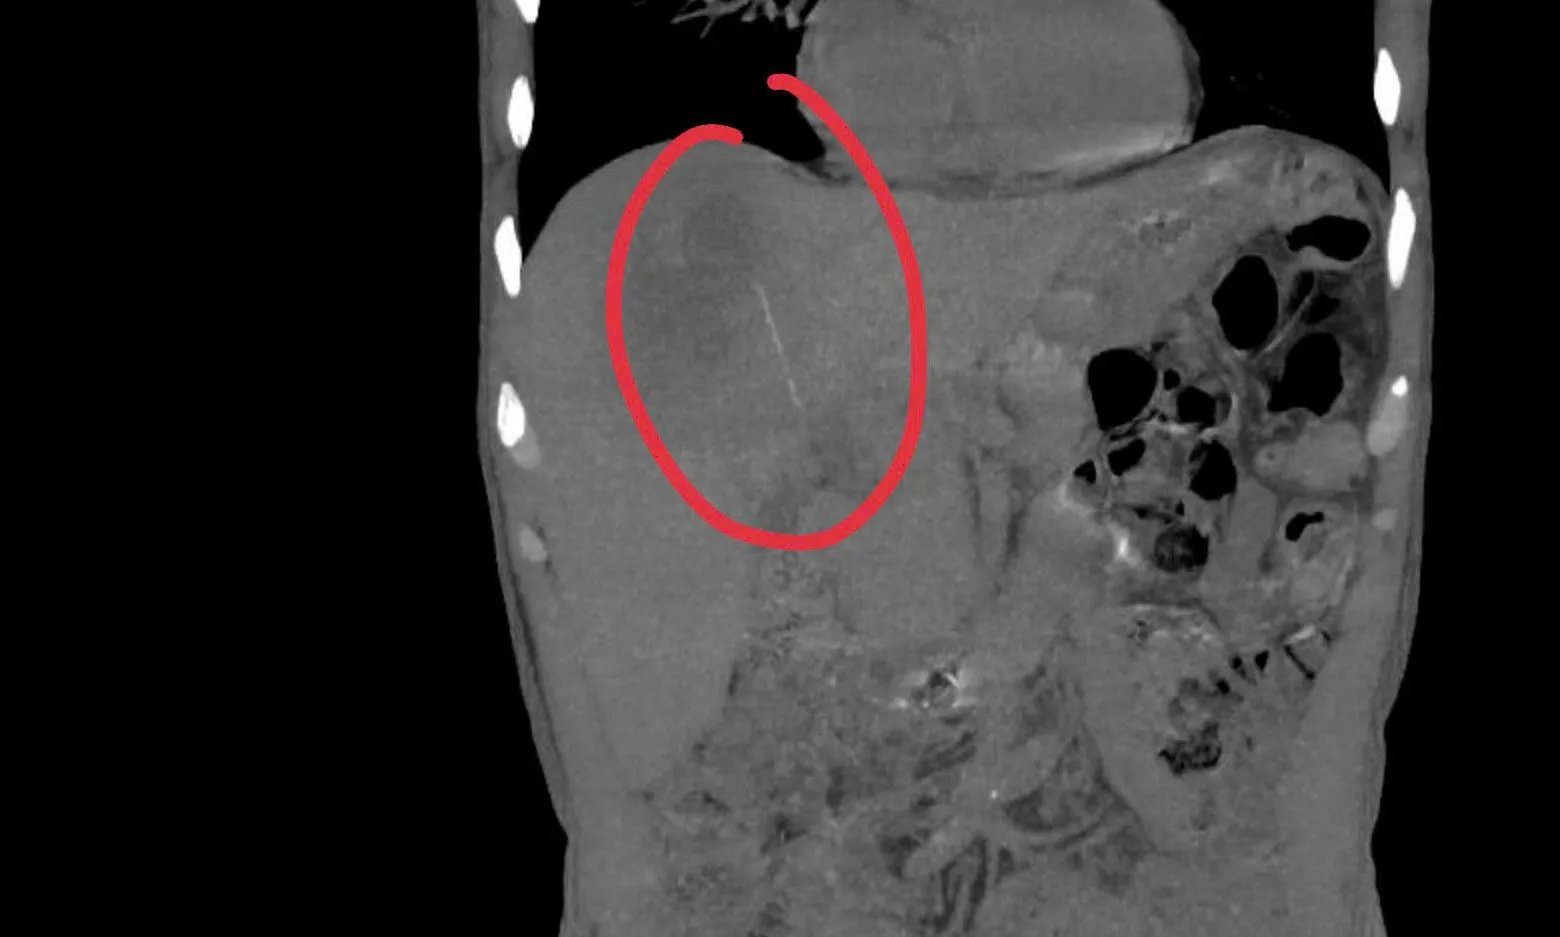

Bệnh nhân nhập viện vì sốt kéo dài, đau thượng vị/hạ sườn phải suốt 1 tháng.

Siêu âm và CT phát hiện dị vật dạng que 6-7cm trong gan, gây áp xe.

Ca phẫu thuật phức tạp đã lấy dị vật (tăm tre) và dẫn lưu áp xe.

Dị vật có thể do thói quen ngậm tăm. Bệnh nhân hồi phục tốt, xuất viện sau 6 ngày.